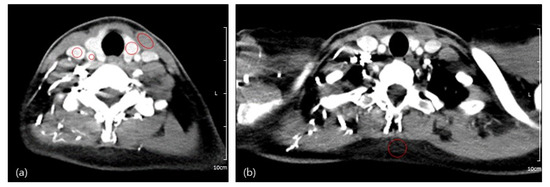

The quantitative analysis results are summarized in Table 5. The mean attenuation value was significantly higher for Group B than Group A for the SCM, IJV, CCA, and thyroid gland but not for subcutaneous fat. When Group a and Group b were compared, there was no statistical difference in attenuation, CNR, and SNR for all estimated structures (Figure 4).

Figure 4.

Differences in SNR and CNR between (a) Group A and B; and (b) Group a and b. * = p-value < 0.05, Student’s t-test.